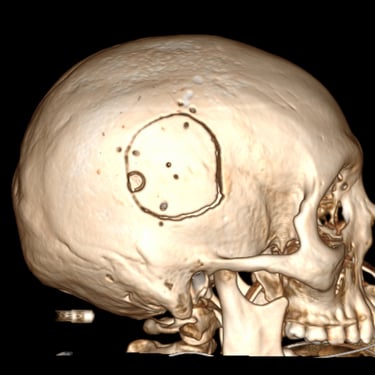

Hemorragia Intracerebral: Craneotomía y Evacuación del Hematoma

La hemorragia intracerebral es una emergencia neurológica grave que requiere diagnóstico rápido y tratamiento oportuno. Cuando el hematoma produce efecto de masa, deterioro del estado de conciencia o riesgo de herniación, la craneotomía y evacuación quirúrgica se convierten en la opción indicada. Este procedimiento permite abrir la bóveda craneal, retirar el coágulo y disminuir la presión intracraneal, preservando la función neurológica. Su objetivo es detener el daño secundario, mejorar la perfusión cerebral y estabilizar al paciente. La intervención temprana, combinada con cuidados críticos especializados, aumenta las posibilidades de supervivencia y recuperación funcional en este tipo de emergencia.